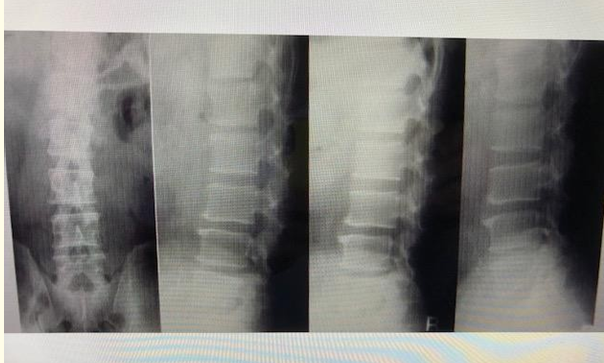

Long-term Course in a Patient with a Broken U-stabilizing Device in the Lumbar Spine

Fumihiko Hara, Masakatsu Saitoh, Masamichi Oh, Ichiro Miyagi, Jin Nakashima, Sei Mihira, Wataru Shimada and Hiraku Kikuchi. 13(11): 20-25.